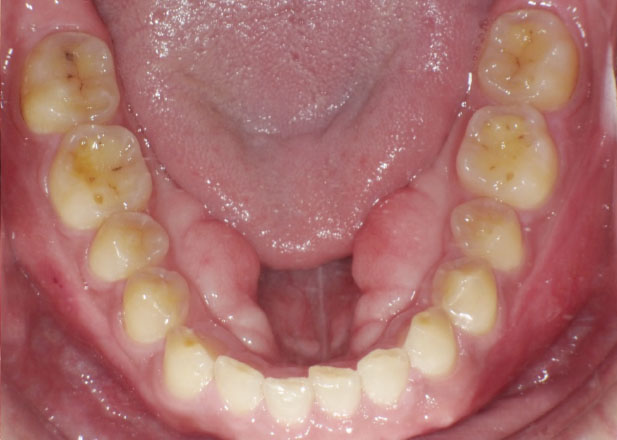

口腔内写真

治療前